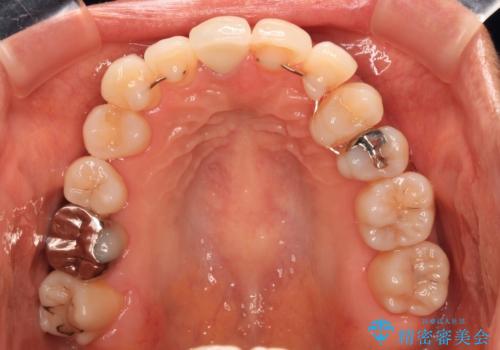

失活により変色した前歯 オールセラミッククラウンによる審美歯科治療

オールセラミッククラウンにて補綴治療を行うこととしました。

周りの歯と調和した、自然な仕上がりとなりました。